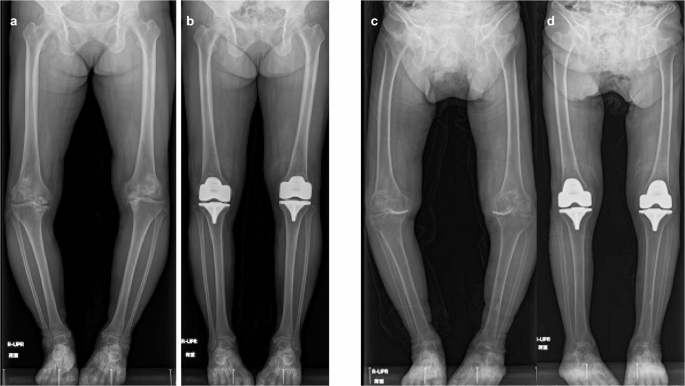

The mean and SD of the changed HKAA values at the postoperative time point were 10.9° and 5.9°, respectively. Figure 3 illustrates the findings of two representative patients showing the effects of manual rKA-TKA with the modified STRT on postoperative HKAA.

Representative pre- and postoperative radiographic findings. (a,b) Findings of a 61-year-old female. Preoperative HKAA were −21° (right) and −18° (left) varus, respectively. Postoperative HKAA are −5°(right) and −3° (left) varus, respectively. In the right knee, 9 mm of the medial bearing and 10 mm of the lateral bearing are used. In left knee, 9 mm of the medial and lateral bearing are used. (c,d) Findings of a 91-year-old female. Preoperative HKAA are −27°(right) and −22° (left) varus, respectively. Postoperative HKAA are −5°(right) and −3° (left) varus, respectively. The medial and lateral bearing of 9 mm are used in both the knees. HKAA hip–knee–ankle angle.